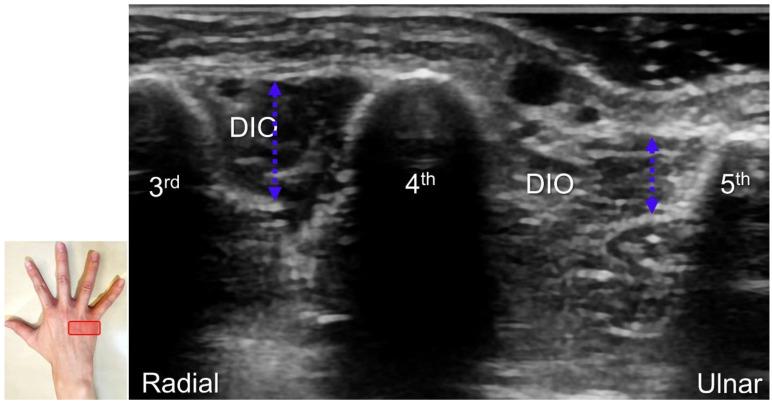

超声已成为一种极具价值的工具,用于腕部区域周围神经病变的成像,特别是对于诸如腕管综合征和尺神经管综合征等常见病症。大量研究表明,神经在卡压部位近端肿胀、边界不清和平扁是神经卡压的特征。然而,关于腕部和手部的小神经或终末神经的信息却很匮乏。本文旨在通过全面概述这些神经卡压的扫描技术、病理学和引导注射方法来填补这一知识空白。本综述详细阐述了正中神经(主干、掌皮支和返支)、尺神经(主干、浅支、深支、掌尺皮支和背尺皮支)、桡浅神经、骨间后神经、掌总/指固有神经和背总/指固有神经。一系列超声图像用于详细说明这些技术。最后,超声检查结果补充了电诊断研究,有助于更好地理解整个临床情况,而超声引导下的干预措施对于治疗相关神经病变是安全有效的。